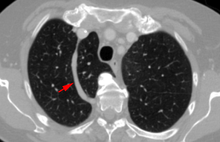

In human anatomy, an azygos lobe is a congenital variation of the upper lobe of the right lung.It is seen in 1% of the population. Embryologically, it arises from an anomalous lateral course of the azygos vein in a pleural septum within the apical segment of the right upper lobe or in other words an azygos lobe is formed when the right posterior cardinal vein, one of the precursors of the azygos vein, fails to migrate over the apex of the lung and penetrates it instead, carrying along two pleural layers that invaginates into the upper portion of the right upper lobe . As it has no bronchi, veins and arteries of its own or corresponding alteration in the segmental architecture of the lung, so it is not a true (misnomer), or even accessory, pulmonary lobe, but rather an anatomically separated part of the upper lobe. It is usually an incidental finding on chest x-ray or computed tomography and is as such not associated with any morbidity but can cause technical problems in thoracoscopic procedures .